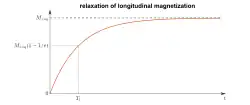

During nuclear magnetic resonance observations, spin–lattice relaxation is the mechanism by which the longitudinal component of the total nuclear magnetic moment vector (parallel to the constant magnetic field) exponentially relaxes from a higher energy, non-equilibrium state to thermodynamic equilibrium with its surroundings (the "lattice"). It is characterized by the spin–lattice relaxation time, a time constant known as T1.

T1 characterizes the rate at which the longitudinal Mz component of the magnetization vector recovers exponentially towards its thermodynamic equilibrium, according to equation Or, for the specific case that

It is thus the time it takes for the longitudinal magnetization to recover approximately 63% [1-(1/e)] of its initial value after being flipped into the magnetic transverse plane by a 90° radiofrequency pulse.